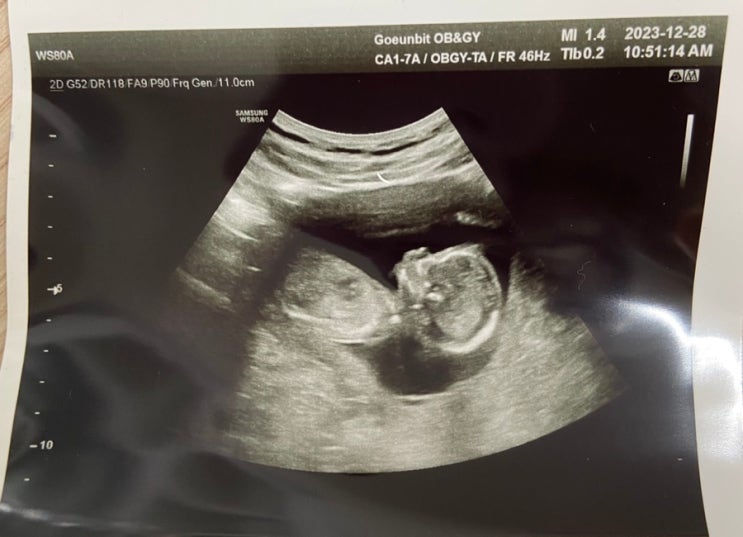

[난임-> 산전 육아 휴직] 강남차에서 송파고은빛으로 전원! #임신 9주차 #강남차 아쉬운 점

너무 오랜만에 포스팅이네요…사실 임신하고 입덧하느라 요즘 몸이 말이 아닙니다 ㅠ 시험관도 힘들다 생각...